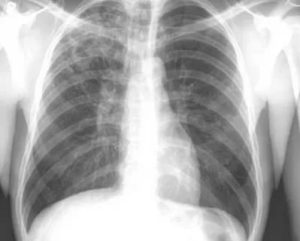

Рентгенография показывает тени органов грудной клетки и их расположение друг относительно друга. Более плотные органы создают большую тень, воздушные – меньшую.

Поскольку рентгеновская пленка является негативом действительного снимка, затемнением называют светлые структуры, дающие большую тень, просветлением – темные воздушные структуры.

Корень легкого выглядит как затемнение на фоне легочной ткани. Его можно обнаружить на границе легких и средостения на уровне I-IV ребра.

На рентгене большую часть тени корня создают артерии, поскольку они имеют большую плотность по сравнению с другими элементами. Бронхи содержат воздух, потому их различают по полоскам просветления на фоне сосудистого рисунка.